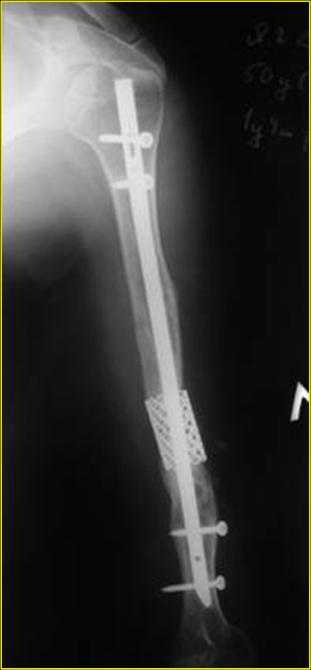

Типичная положительная ситуация для интрамедуллярного остеосинтеза с

использованием опорного металлокаркаса для компенсации дефекта.

Послеоперационное ведение активное или агрессивно-активное. Каркасы

можно заказать в МАТИ.

Рентгеновская версия реконструкции. хронология:

после операции, 2 мес. после операции, через 1 год

Движения в полном объеме восстановлены к 2 мес. после операции. Если надо могу показать мультик. Сейчас уже прошло более 3 лет, больная не

показывается. Успехов ЛАФ.